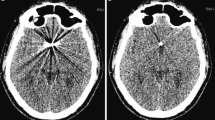

To emphasize the benefit of the WARP sequences in reducing metal artifacts, we present an exemplary case. Almost 10 years ago, a patient was surgically treated for a symptomatic cavernoma in the right basal ganglia and the frontal pole of the temporal lobe (Fig. 4a). Then 5 years later, a benign aneurysm of the right middle cerebral artery was diagnosed and treated by surgical clipping. The follow-up MRI imaging of the former cavernoma site was markedly impaired by the large metal artifacts (Figs. 4b and 4d). With the new WARP sequences presented here, the entire resection area could be clearly assessed and no evidence of a recurrence of the cavernoma could be found (Figs. 4c and 4e).

The case of a patient initially treated for a symptomatic cavernoma (a; T2* weighted image). A few years later, the patient was treated for a right-sided MCA aneurysm by surgical clipping. In the follow-up MRI scans, large metal artifacts compromised the site of the former cavernoma (b, d; T2w TSE). With the WARP TSE sequences it is now possible to evaluate the entire site of the former cavernoma without interference from artifacts (c, e; T2w WARP TSE)